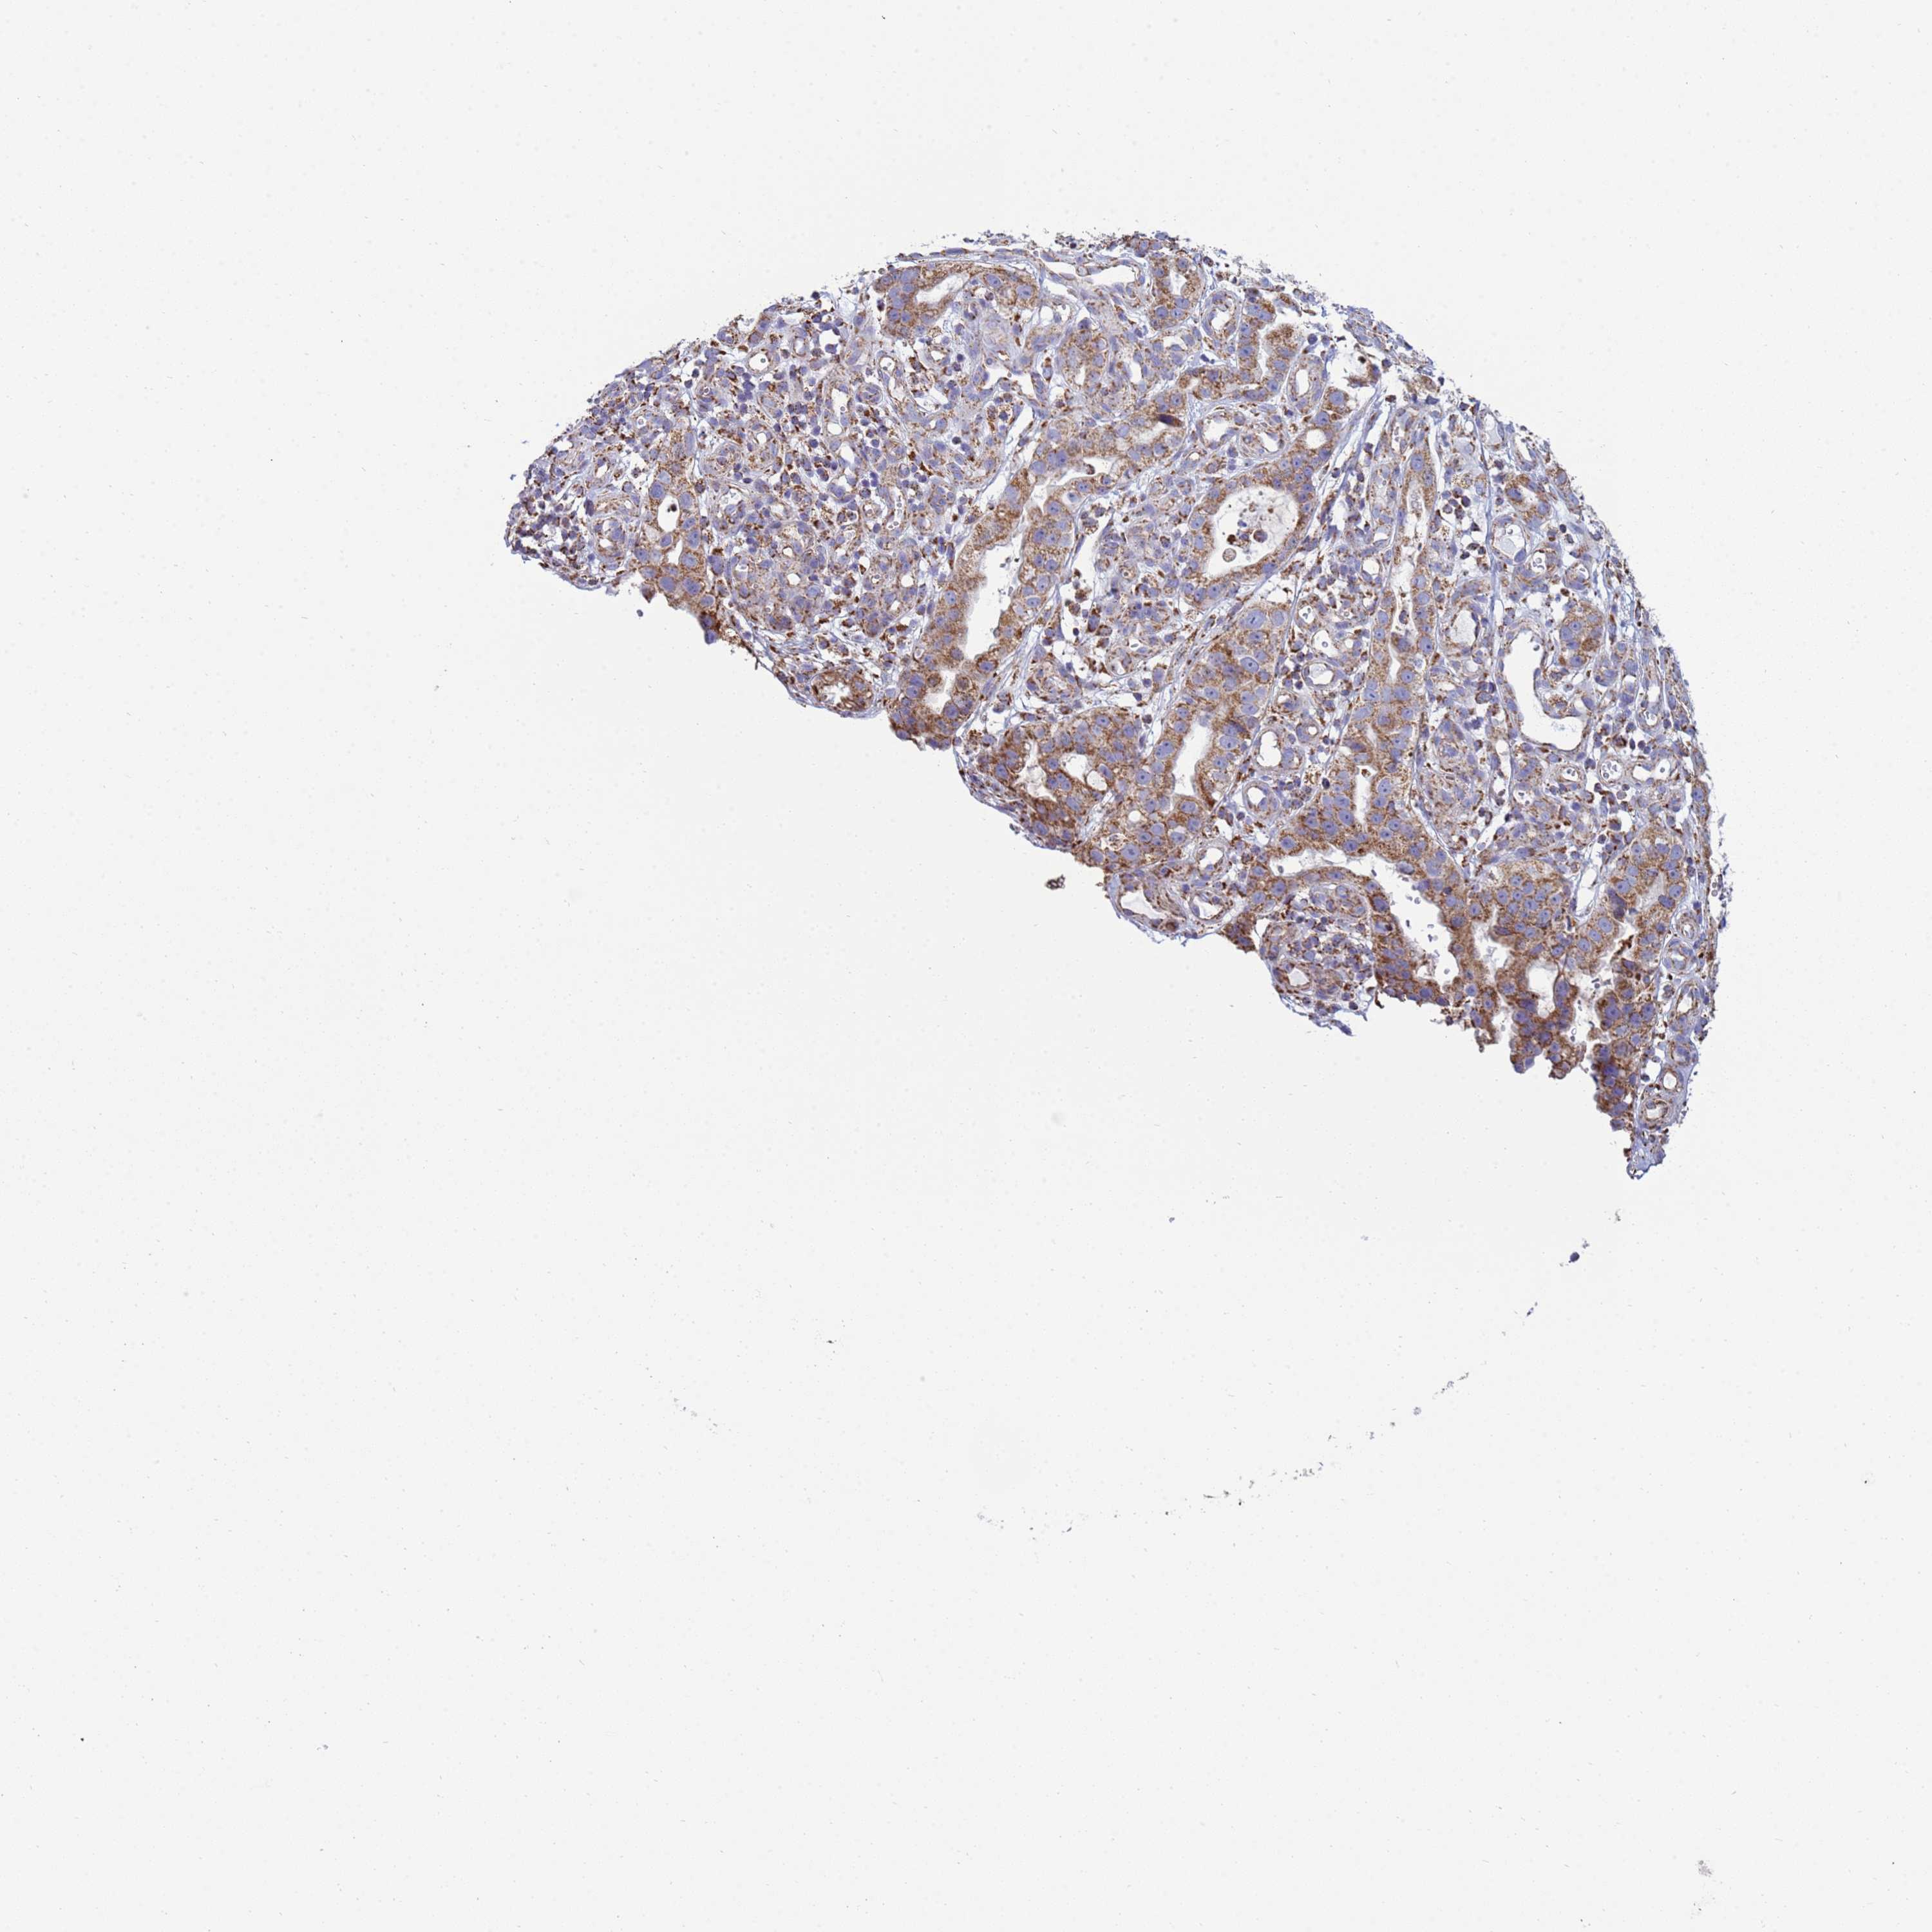

STOMACH CANCER - Protein expressioni

A mouse-over function shows sample information and annotation data. Click on an image to view it in a full screen mode. Samples can be filtered based on level of antibody staining by selecting one or several of the following categories: high, medium, low and not detected. The assay and annotation is described here.

Note that samples used for immunohistochemistry by the Human Protein Atlas do not correspond to samples in the TCGA dataset.

Antibody stainingi

Antibody staining in the annotated cell types in the current human tissue is reported as not detected, low, medium, or high, based on conventional immunohistochemistry profiling in selected tissues. This score is based on the combination of the staining intensity and fraction of stained cells.

Each image is clickable and will lead to virtual microscopy that enables deeper exploration of all samples and also displays staining intensity scores, fraction scores and subcellular localization as well as patient and tissue information for each sample.

Antibody HPA042945

Staining

High

Medium

Low

Not detected

Intensity

Strong

Moderate

Weak

Negative

Quantity

>75%

75%-25%

<25%

None

Location

Nuclear

Cytoplasmic/membranous

Cytoplasmic/membranous,nuclear

Adenocarcinoma, NOS